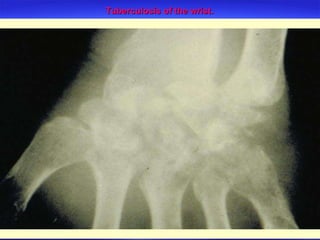

Tuberculosis of the wrist.